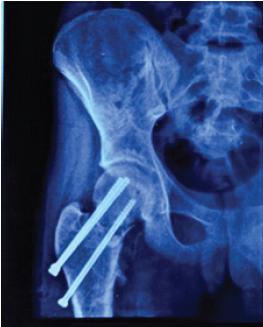

Aneurysmal Bone Cyst Presenting as a Pathological Subtrochanteric Femur Fracture in an Adolescent: A Case Report

Chandrashekhar R Rai , Sandeep V Gavhale , Vijaysing Chandele , Alok P Yadav , Chinmay S Torne , Vishal B Karpe

………………………………p.89-93